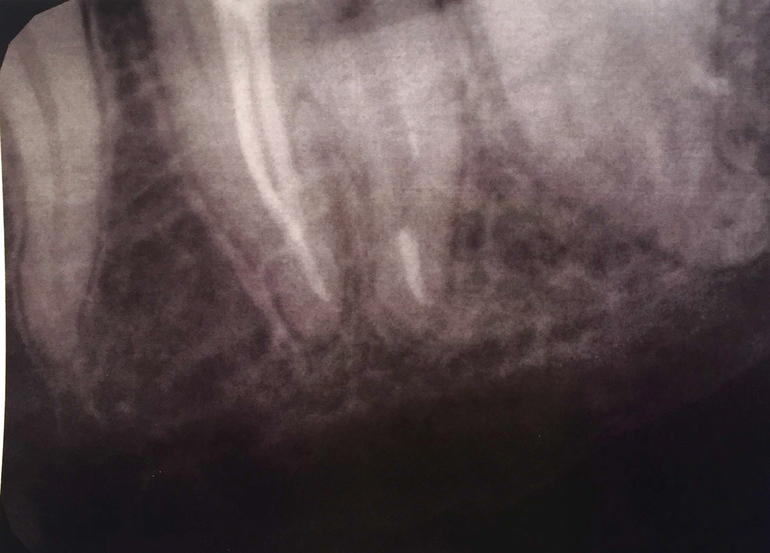

Ночью не выдержала, нашла радиовизиограф, сделала снимок, который прилагаю.